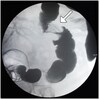

What pathology is shown here?

Tracheaoesophageal fistula

What are the white arrows pointing to?

The airway